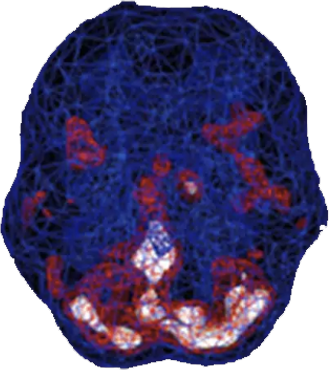

SPECT (single photon emission computed tomography) is a nuclear medicine study that evaluates blood flow and activity in the brain. Basically, it shows three things: healthy activity, too little activity, or too much activity. A healthy “active” scan shows the most active parts of the brain with blue representing the average activity and red (or sometimes red and white) representing the most active parts of the brain. In the healthy scan on the top right, the most active area is in the cerebellum, at the back/bottom part of the brain. In the brain scan below it of a woman with postpartum depression, there is excessive activity in the deep limbic system—the brain’s emotional center.

Healthy Brain Scan

Postpartum Depression

Brain Scan